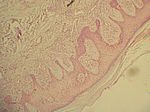

Ulcus cruris, HE